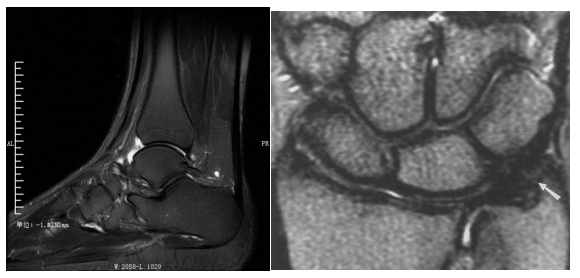

磁共振胰胆管水成像(MRCP)

胆总管结石(MRCP)